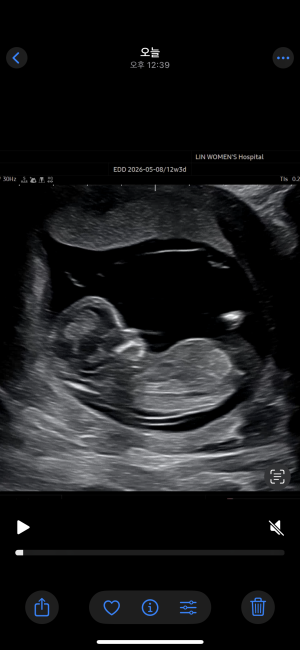

9주차 둘째에요

또치25

2025-04-14

20

6